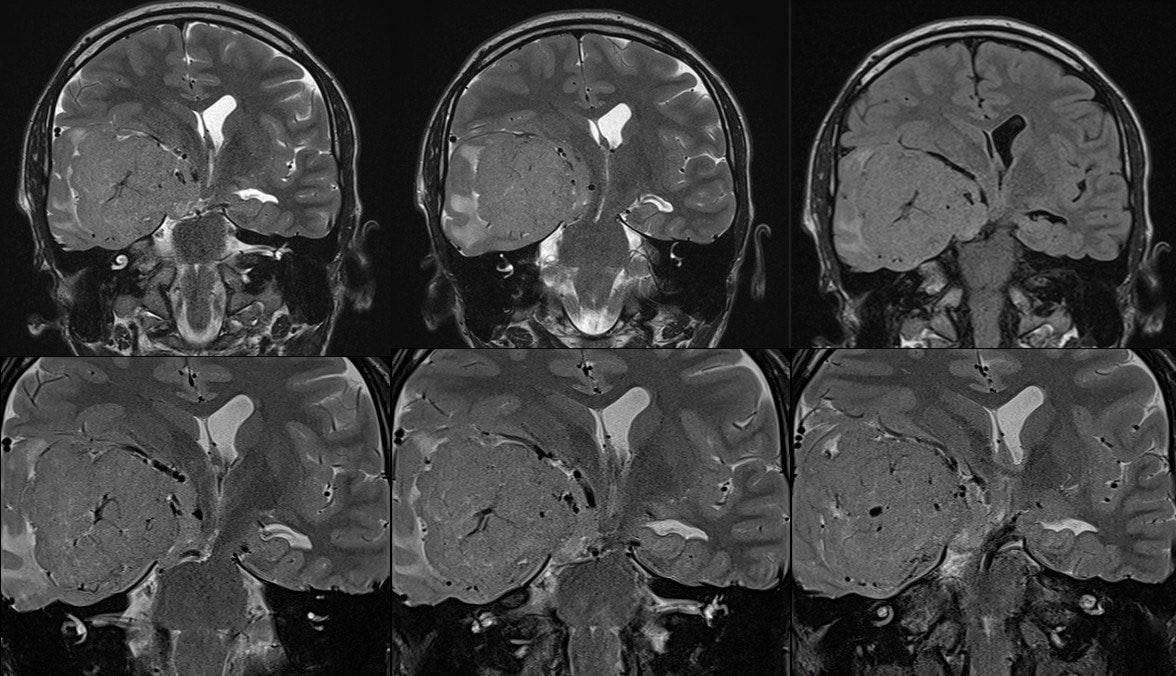

Изображение